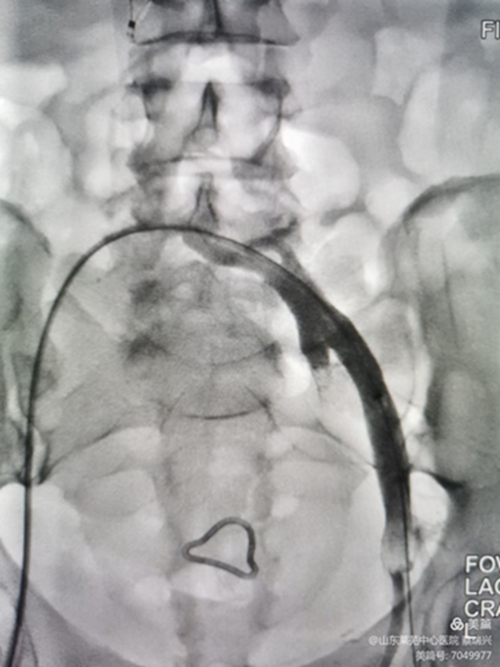

取出濾器,預(yù)行左髂總靜脈成形術(shù),但又閉塞,導(dǎo)管不能通過。

釋放支架,行后擴(kuò)張,球囊有“腰征",且很窄,考慮閉塞段像"噗"一樣。

噗征